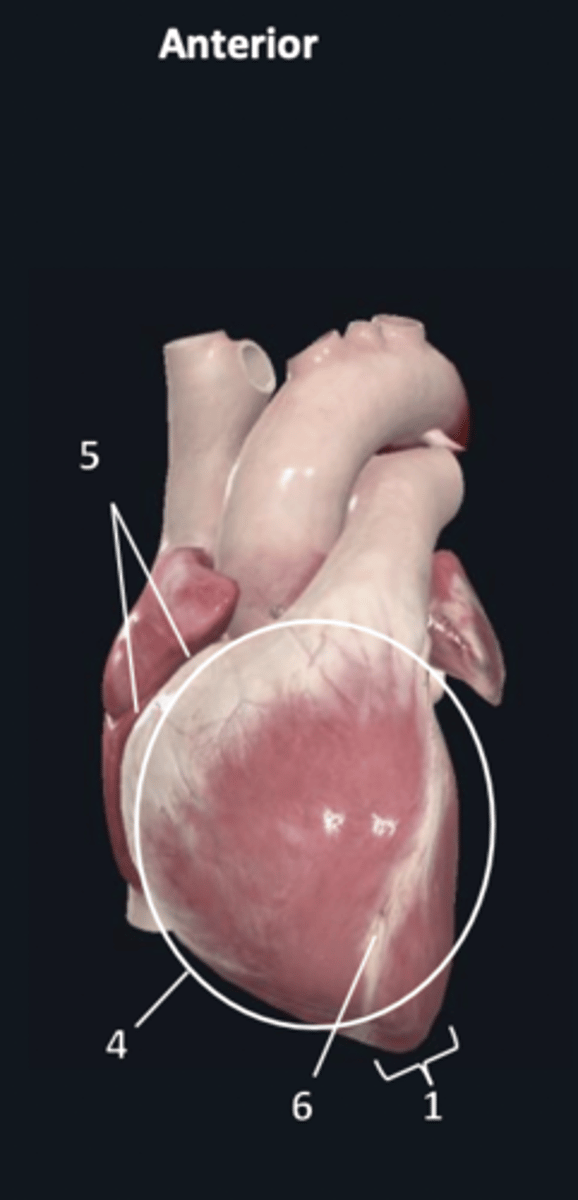

apex

1

sternocostal surface

4

atrioventricular groove

5

anterior interventricular sulcus

6